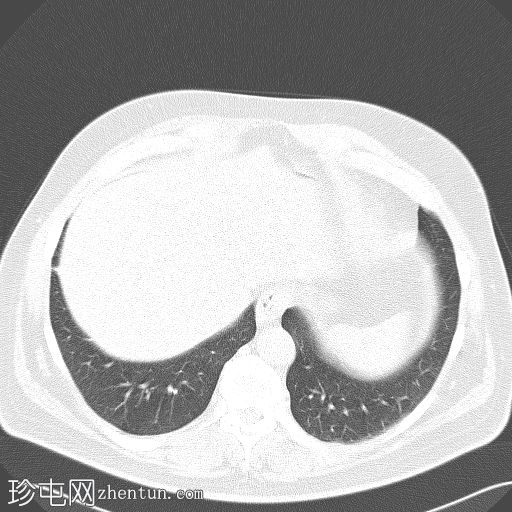

轴位

5.jpg

盆腔内可见一大小为12 x 17 cm的边界清晰的异质性软组织肿块,向下延伸至下腹部。肿块内未见钙化或脂肪密度影。肿块向下推挤膀胱,并牵拉周围肠袢,但无放射学侵犯证据。未见明显淋巴结肿大、腹水或气腹。未见肺部或骨骼局灶性病变。肝脏可见数个小的单纯性囊肿。患者存在少量Bosniak I型肾囊肿,双侧肾盂肾盏系统饱满。曾行胆囊切除术。